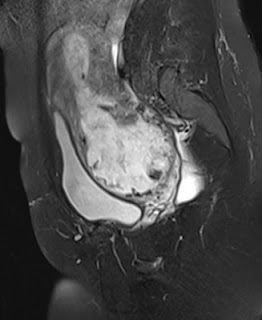

| Figure 3 |

Figures 1 to 5 ( T1, STIR coronal images) show cartilaginous

intra-articular masses or overgrowth along with ossification arising from the

medial aspect of left distal femoral, proximal tibial and distal tibial

epiphyses with resultant deformity of the knee and ankle joints and limb length

discrepancy. This fits into the classic form of Trevor Fairbank disease/

Dysplasia sepiphysealis hemilelica.